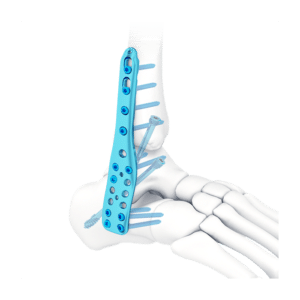

CLAVO PARA ARTRODESIS DE TOBILLO

El clavo para artrodesis de tobillo está diseñado para deformidades y artritis graves del pie y el tobillo.